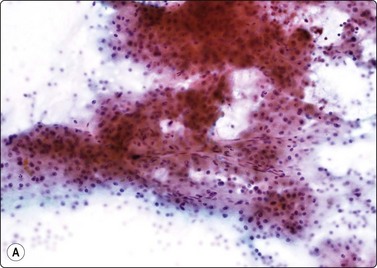

Normal structures (Fig. 10.1)

Cytologic features

Hepatocytes mainly in cohesive sheets; some smaller cell aggregates and few single-lying cells,

Kupffer cells and sinusoidal endothelial cells,

Bile duct epithelium.

Fig. 10.1 Hepatocytes

(A) Irregular cohesive sheet showing a trabecular arrangement (Pap, IP); (B) Cohesive groups of polygonal cells with abundant sometimes vacuolated granular cytoplasm (Pap, HP); (C) Cohesive cells with central round nuclei, granular cytoplasm and indistinct cell borders; note the small wedge-shaped Kupffer cell (arrow) (MGG, HP).

Although the aspirate may appear to consist mainly of blood, it usually contains many liver cells. Cell cohesion is particularly strong, and when the needle content is placed on a slide one can often see small, firm, semitranslucent tissue fragments which are difficult to spread. In comparison, tumor tissue fragments are usually soft, fragile and easily smeared.

In smears, normal hepatocytes form irregular, cohesive sheets and narrow cords 1–2 cells thick (Fig. 10.1A). Single cells are infrequent. The cells are large, round or distinctly polygonal in outline with abundant granular cytoplasm, sometimes vacuolated, staining eosinophilic with H&E, blue with Papanicolaou or gray–blue with MGG (Fig. 10.1B). Nuclei are centrally located, round, with finely granular chromatin which is evenly distributed. Binucleate cells are common. Nucleoli are central and usually small although prominent. The cell membrane is indistinct. Normal hepatocytes may display mild to moderate anisokaryosis due to polyploidy, increasing with the patient’s age. Occasional nuclei may be very large in non-neoplastic liver tissue. Coarse, granular intracytoplasmic pigment is commonly present in hepatocytes. It stains green–black with MGG, brown with H&E and is probably lipofuscin rather than bile. Kupffer cells can usually be found and appear as single, bare, comma-shaped nuclei between the hepatocytes. Bile duct epithelial cells form small, regular monolayered sheets. They are palisaded when seen from the side. The cytoplasm is minimal, nuclear chromatin is granular and nucleoli are inconspicuous. These are few in number in samples from normal liver tissue.